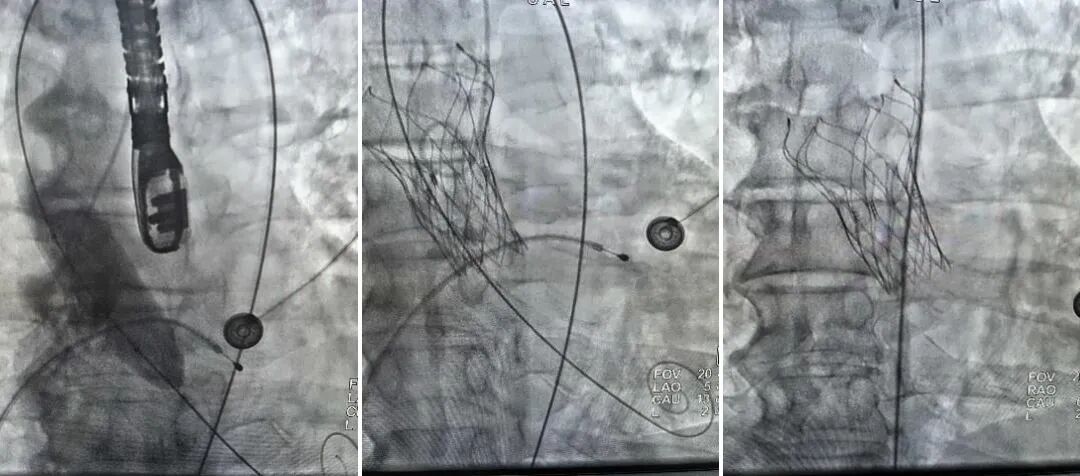

当被告知需要行外科开胸手术进行瓣膜置换时,其家属因外科手术创伤大,不愿行开胸手术。面对挑战,经开院区心血管内科一病区迎难而上,联合超声医学科、麻醉科等科室进行了深入细致的术前评估,最终为该患者制定了创伤小、恢复快的经导管主动脉瓣置入术(TAVI)微创手术方案,展现了团队在高危复杂病例处理上的丰富经验与多学科协作优势。

据西安市中心医院经开院区心血管内科一病区主任吴冠吉介绍,TAVI技术作为国际领先的微创介入技术,无需开胸,仅通过血管穿刺即可完成瓣膜置入,极大地为高龄、高危、无法耐受外科手术的患者提供了生的希望。